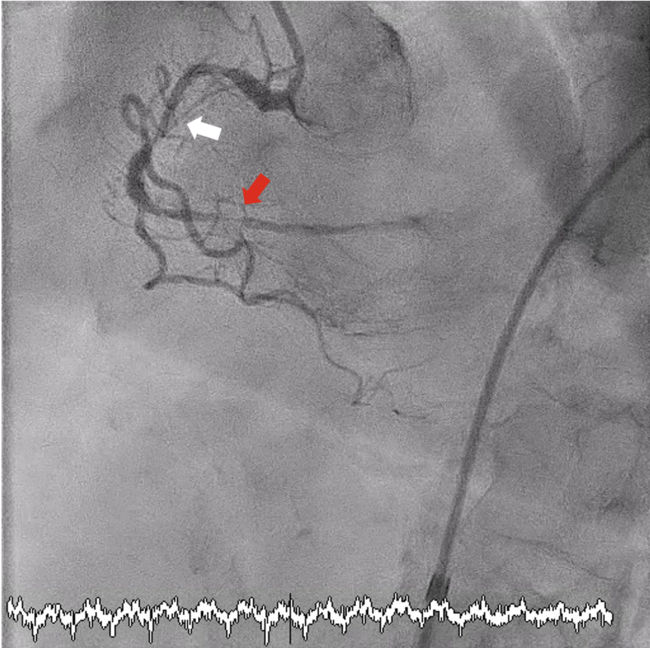

His baseline blood pressure (BP) was 180 to 190/90 to 100 mm Hg. An angiogram confirmed heavy calcification with 80% stenoses in the proximal/mid-RCA and subtotal occlusion distally (Figure 1). PCI was performed via femoral access using a 7F 0.75 Amplatz Left guide catheter (Medtronic). The RCA was successfully wired with a Fielder FC (ASAHI INTECC), supported by a FineCross microcatheter (Terumo). However, neither the microcatheter nor a 1.0 × 10-mm Sapphire balloon (OrbusNeich) could cross the mid-RCA lesion.